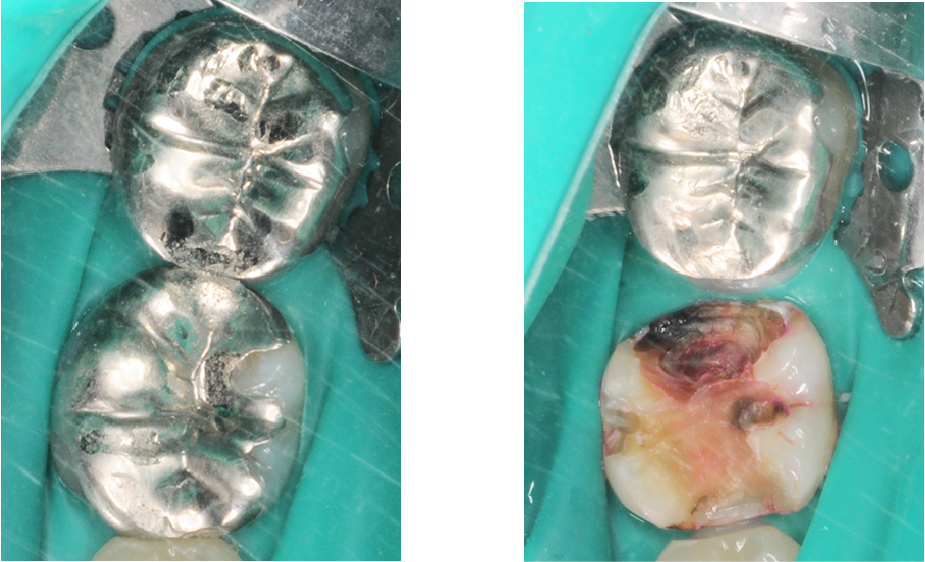

銀歯の中で虫歯が再発した症例01

銀歯の中で虫歯が再発した症例

銀の被せ物を

外した後

銀歯の中で虫歯が再発した症例02

しかし、銀歯と歯の間にわずかな隙間ができやすく、時間が経つとそこから細菌が入り込み、虫歯が再発してしまうことがあります。実際、治療した歯の再発虫歯は少なくありません。